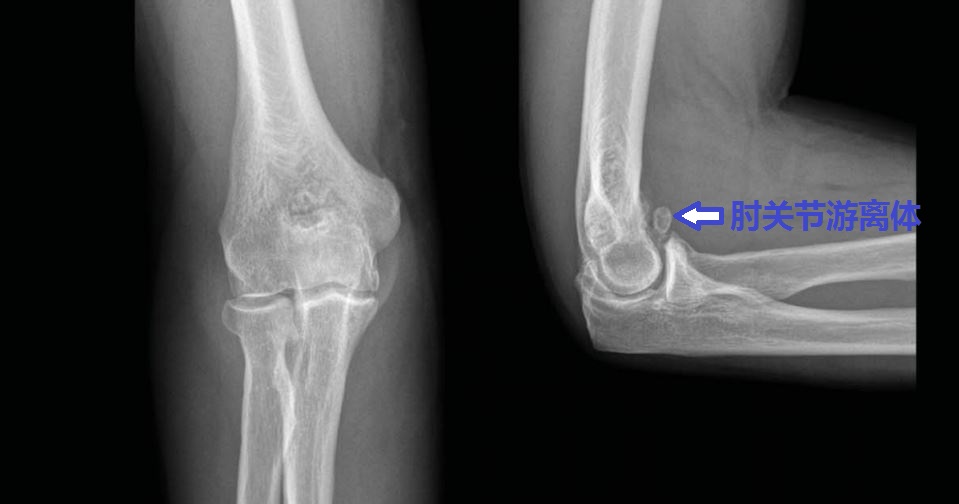

为什么您的肘关节伸不直呢?

伸不直往往是因为:1、尺骨鹰嘴骨质增生;2、肱骨远端后侧的尺骨鹰嘴窝骨质增生填塞;3、肘关节前侧的关节囊挛缩;4、肘关节内的游离体卡住了;等等。

为什么您的肘关节屈不下来呢?

屈不下来往往是因为:1、尺骨冠状突骨质增生;3、肱骨远端前面的尺骨冠状突窝骨质增生;4、肘关节后侧的关节囊挛缩;等等。